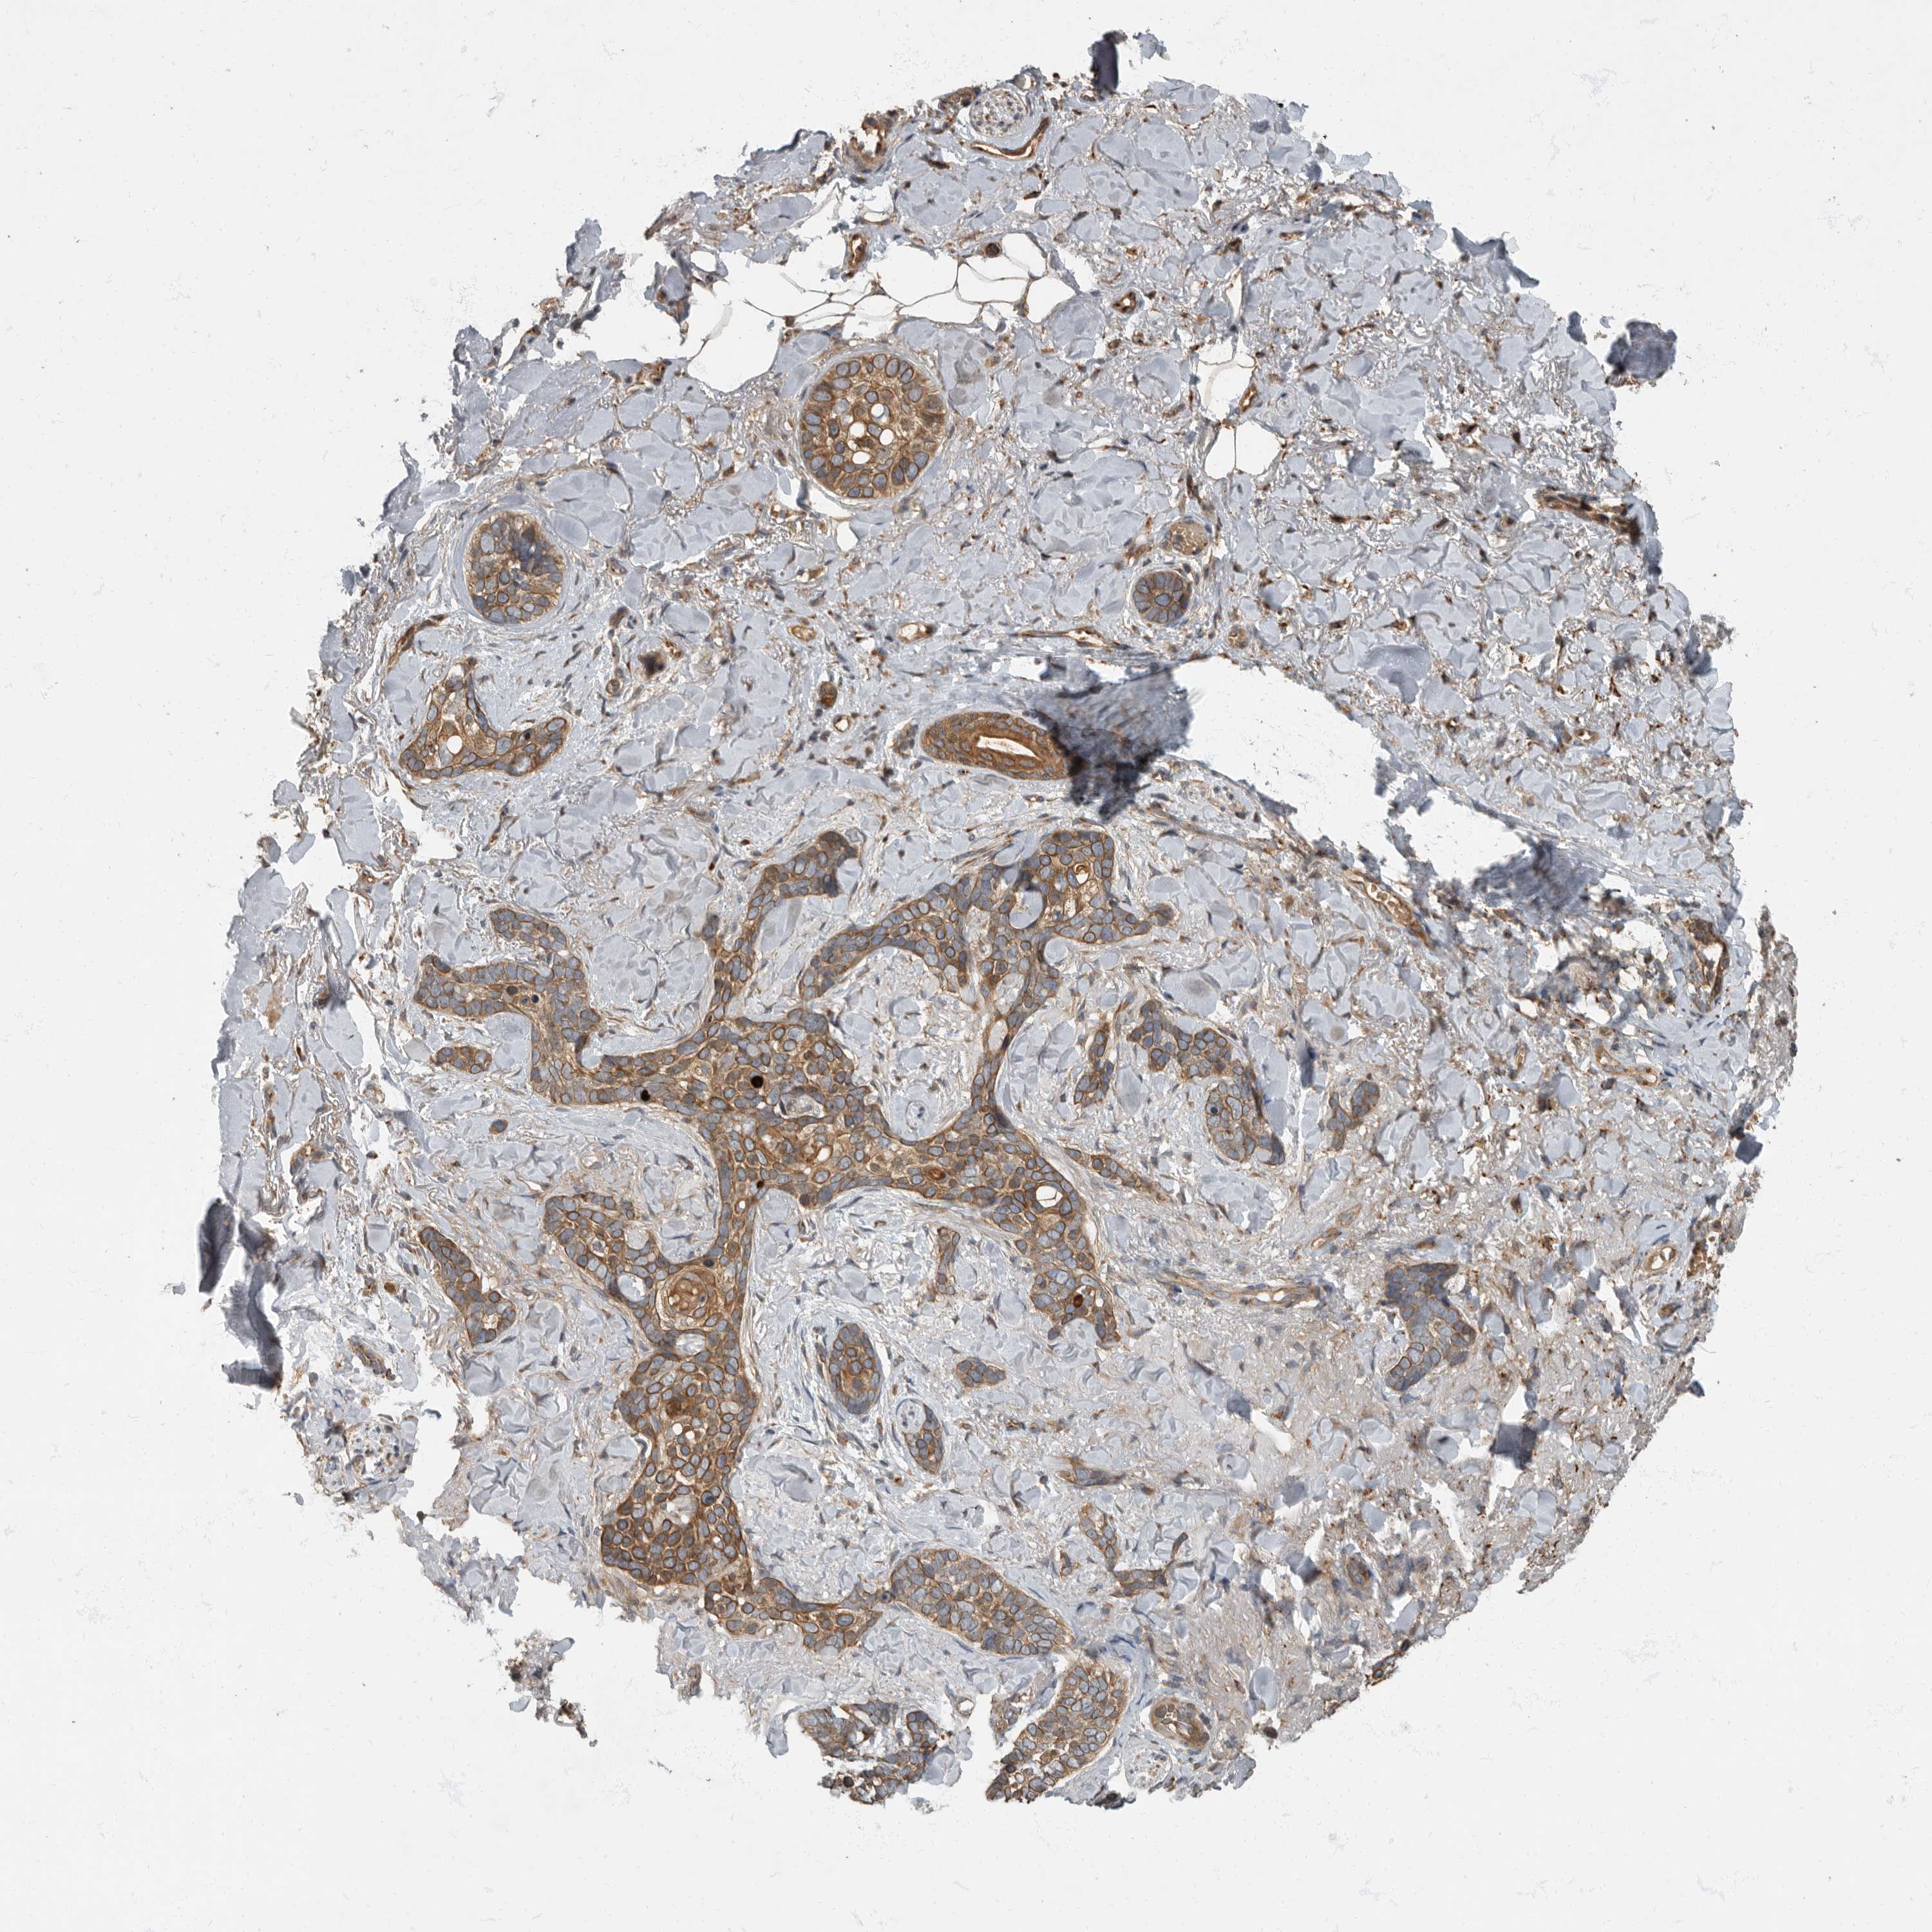

Basal cell and squamous cell cancer

SKIN CANCER - Protein expressioni

A mouse-over function shows sample information and annotation data. Click on an image to view it in a full screen mode. Samples can be filtered based on level of antibody staining by selecting one or several of the following categories: high, medium, low and not detected. The assay and annotation is described here.

Antibody stainingi

Antibody staining in the annotated cell types in the current human tissue is reported as not detected, low, medium, or high, based on conventional immunohistochemistry profiling in selected tissues. This score is based on the combination of the staining intensity and fraction of stained cells.

Each image is clickable and will lead to virtual microscopy that enables deeper exploration of all samples and also displays staining intensity scores, fraction scores and subcellular localization as well as patient and tissue information for each sample.

Antibody HPA026792

Staining

High

Strong

Moderate

Quantity

>75%

Location

Nuclear

Cytoplasmic/membranous

Basal cell carcinoma